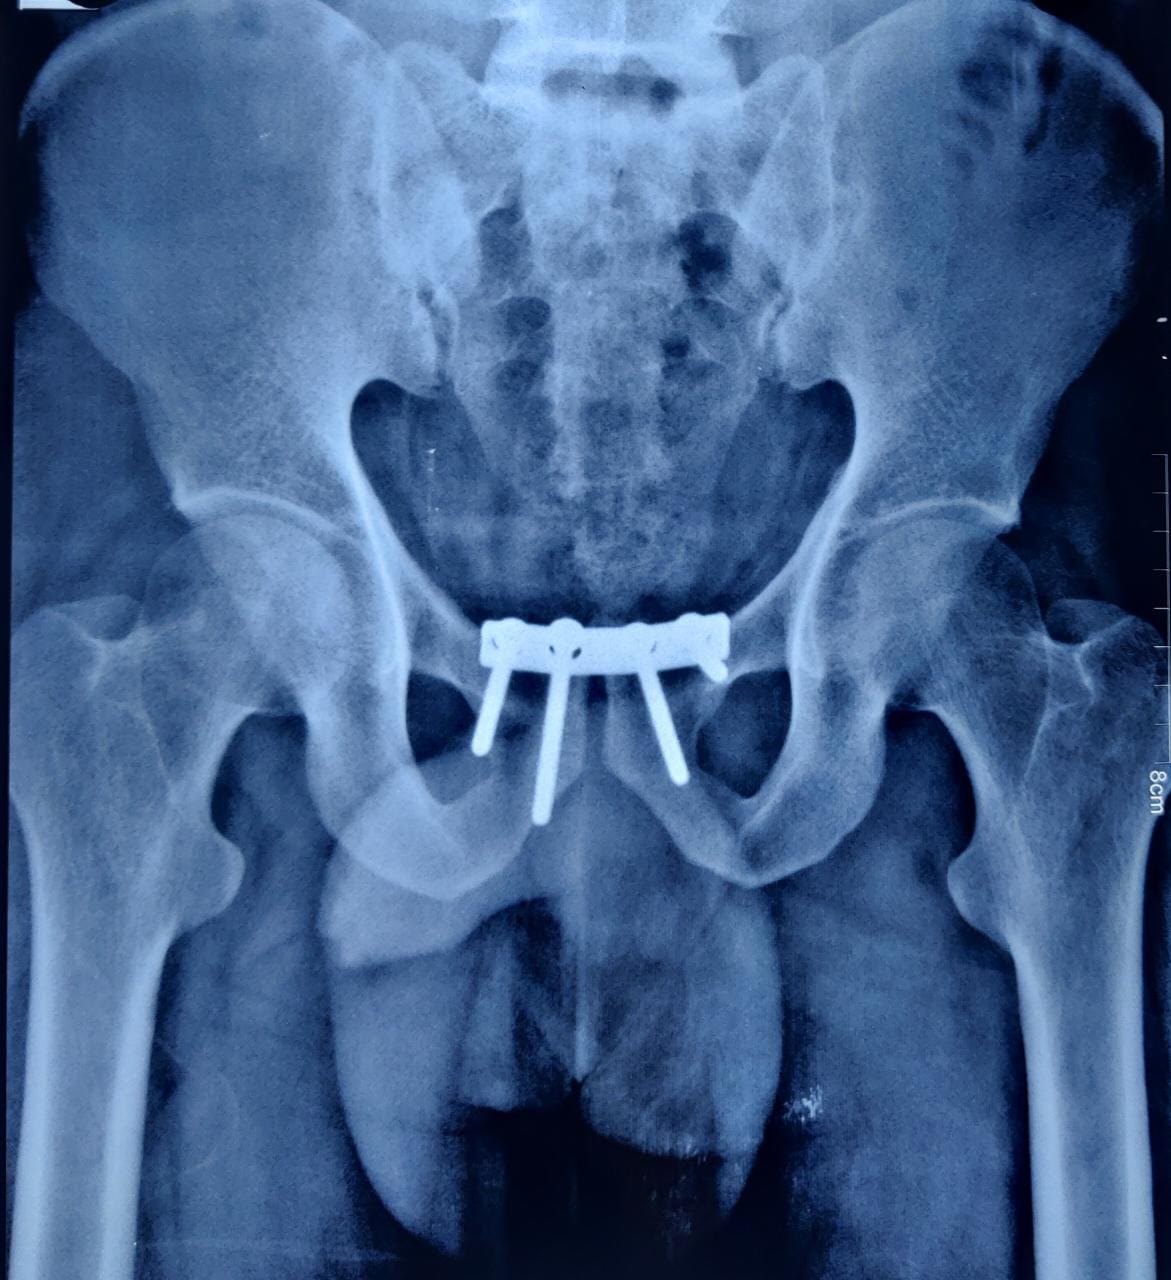

Case 2:- Pubic Diastasis